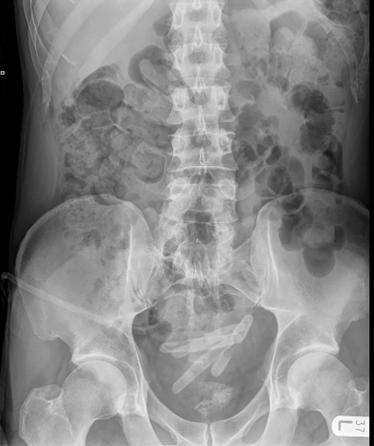

A plain abdominal radiograph (Figure 1) revealed several calcifications in the area of the bladder consistent with bladder calculi. A non-contrast computed tomography scan of the urinary tract confirmed the presence of tubular calcifications in the bladder presumed to be bladder calculi.

Figure 1: Plain abdominal radiograph revealing multiple calcifications in the area of the bladder and a catheterized bladder.